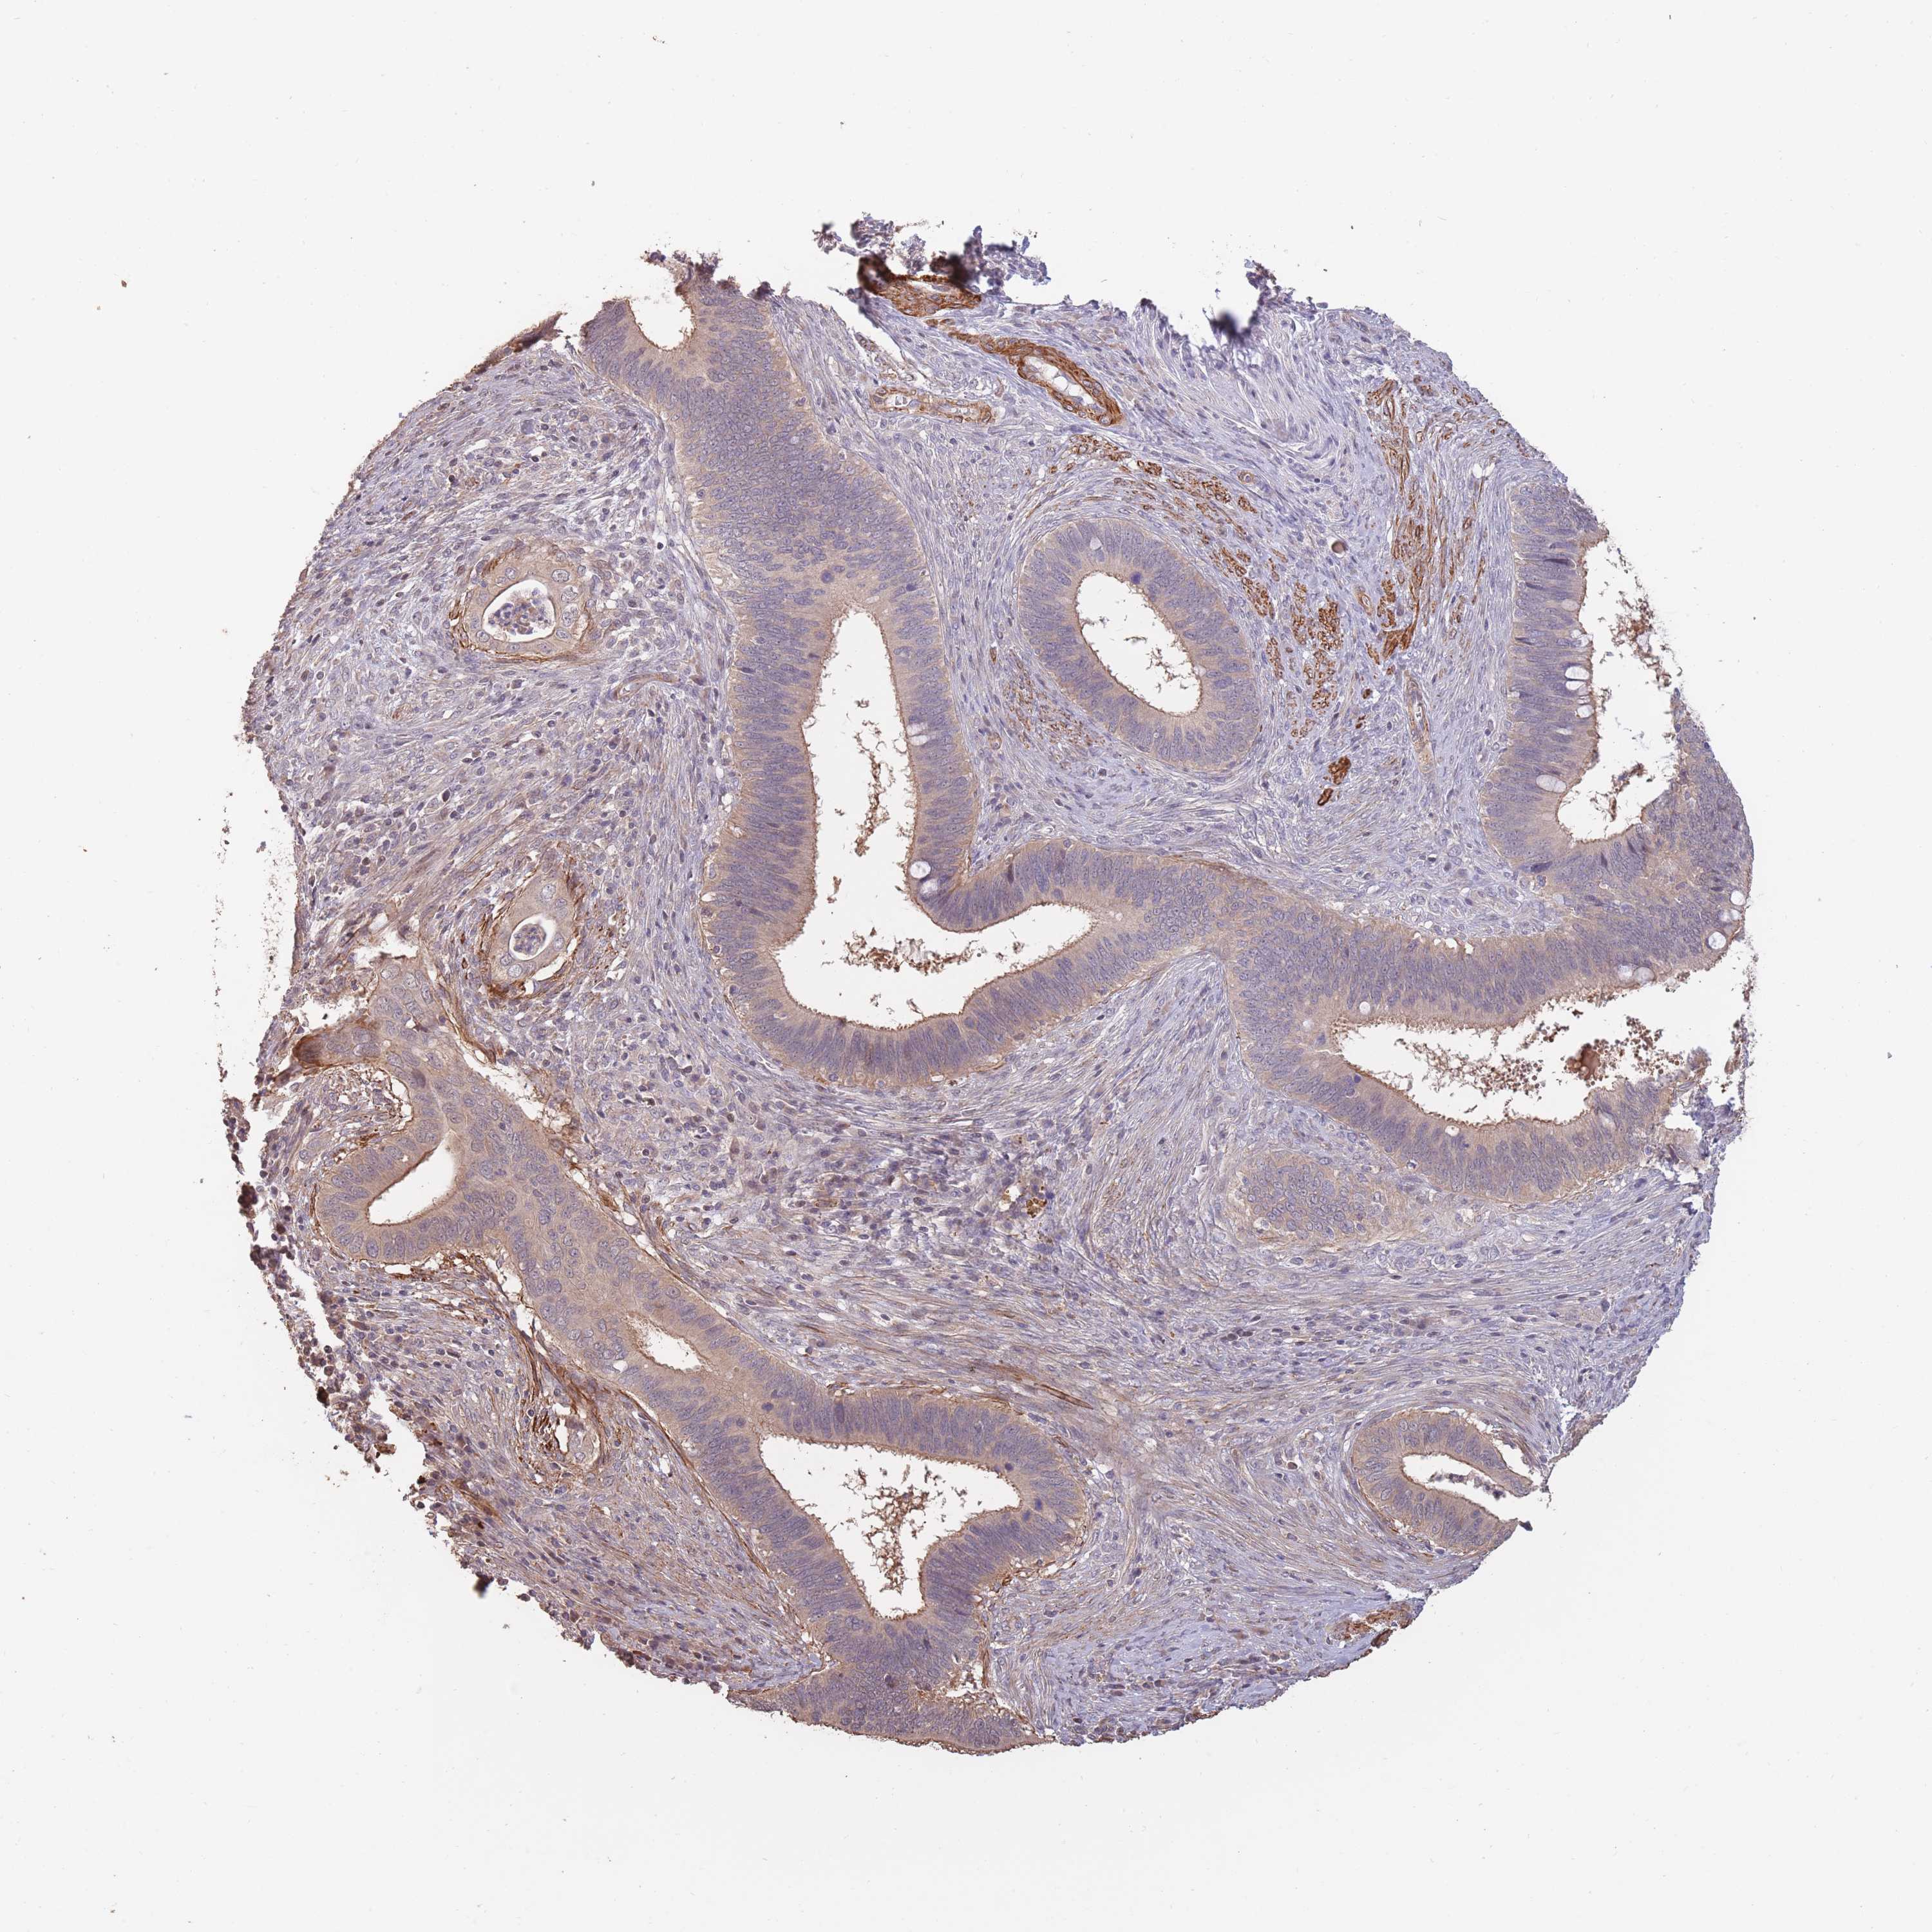

CERVICAL CANCER - Protein expressioni

A mouse-over function shows sample information and annotation data. Click on an image to view it in a full screen mode. Samples can be filtered based on level of antibody staining by selecting one or several of the following categories: high, medium, low and not detected. The assay and annotation is described here.

Note that samples used for immunohistochemistry by the Human Protein Atlas do not correspond to samples in the TCGA dataset.

Antibody stainingi

Antibody staining in the annotated cell types in the current human tissue is reported as not detected, low, medium, or high, based on conventional immunohistochemistry profiling in selected tissues. This score is based on the combination of the staining intensity and fraction of stained cells.

Each image is clickable and will lead to virtual microscopy that enables deeper exploration of all samples and also displays staining intensity scores, fraction scores and subcellular localization as well as patient and tissue information for each sample.

Antibody HPA006592

Staining

High

Medium

Low

Not detected

Intensity

Strong

Moderate

Weak

Negative

Quantity

>75%

75%-25%

<25%

None

Location

Nuclear

Cytoplasmic/membranous

Cytoplasmic/membranous,nuclear

Squamous cell carcinoma, NOS

Adenocarcinoma, NOS